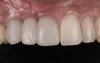

At the patient’s return visit 3 months after implant placement, the composite overlays were removed and the incisal edges of the provisional restoration were modified to approximate the length of the contralateral teeth. The patient reported no complaints, discomfort, or symptomatology throughout the osseointegration period. The implants were stable, and all discernable clinical parameters were within normal limits. The radiographic assessment revealed adequate bone-to-implant contact and osseous crest levels. Similarly, the peri-implant soft tissues displayed a healthy appearance and satisfactory gingival margin architecture (Figure 24 through Figure 27).

The patient subsequently enrolled in medical school, limiting her availability to continue treatment because of academic commitments and geographic location. As a result, she has been maintained with a long-term milled polymethylmethacrylate temporary restoration for an 18-month period and is currently scheduled to return for final impressions and completion of the definitive restoration.

Fig 25. Three months post-treatment, peri-implant soft tissues appeared healthy.

Figure 25

Fig 26 . Three months post-treatment, favorable gingival architecture was preserved.

Figure 26

Fig 27. Three months post-treatment, favorable gingival architecture was preserved.

Figure 27